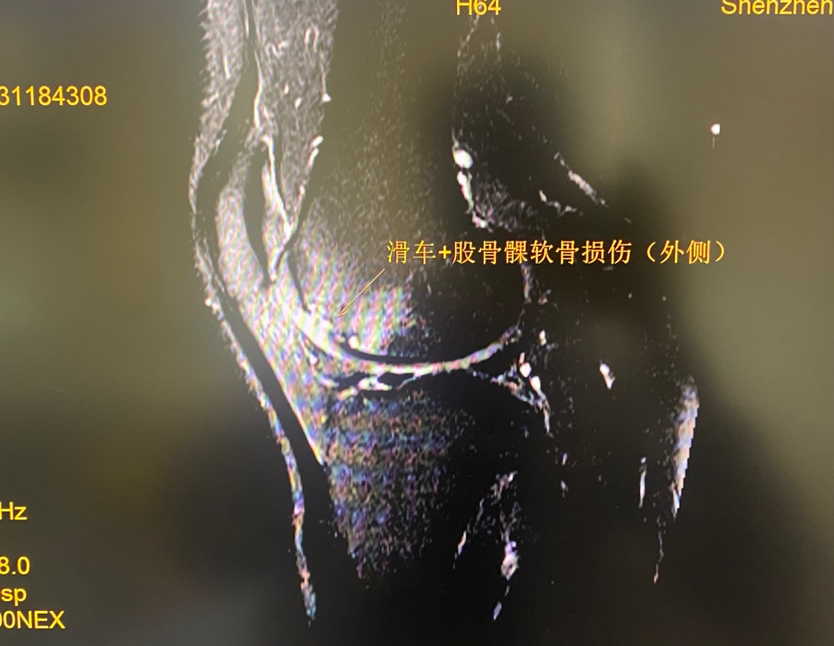

下面展示典型的膝关节软骨损伤,MRI核磁扫描可以清晰发现软骨损伤(3-4度),门诊检查非常常见!